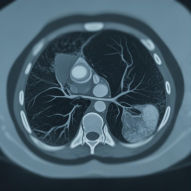

| 협심증 / 심근경색 | 가슴을 쥐어짜는 통증, 식은땀, 호흡곤란 |

심장 혈관(관상동맥) 막힘 |